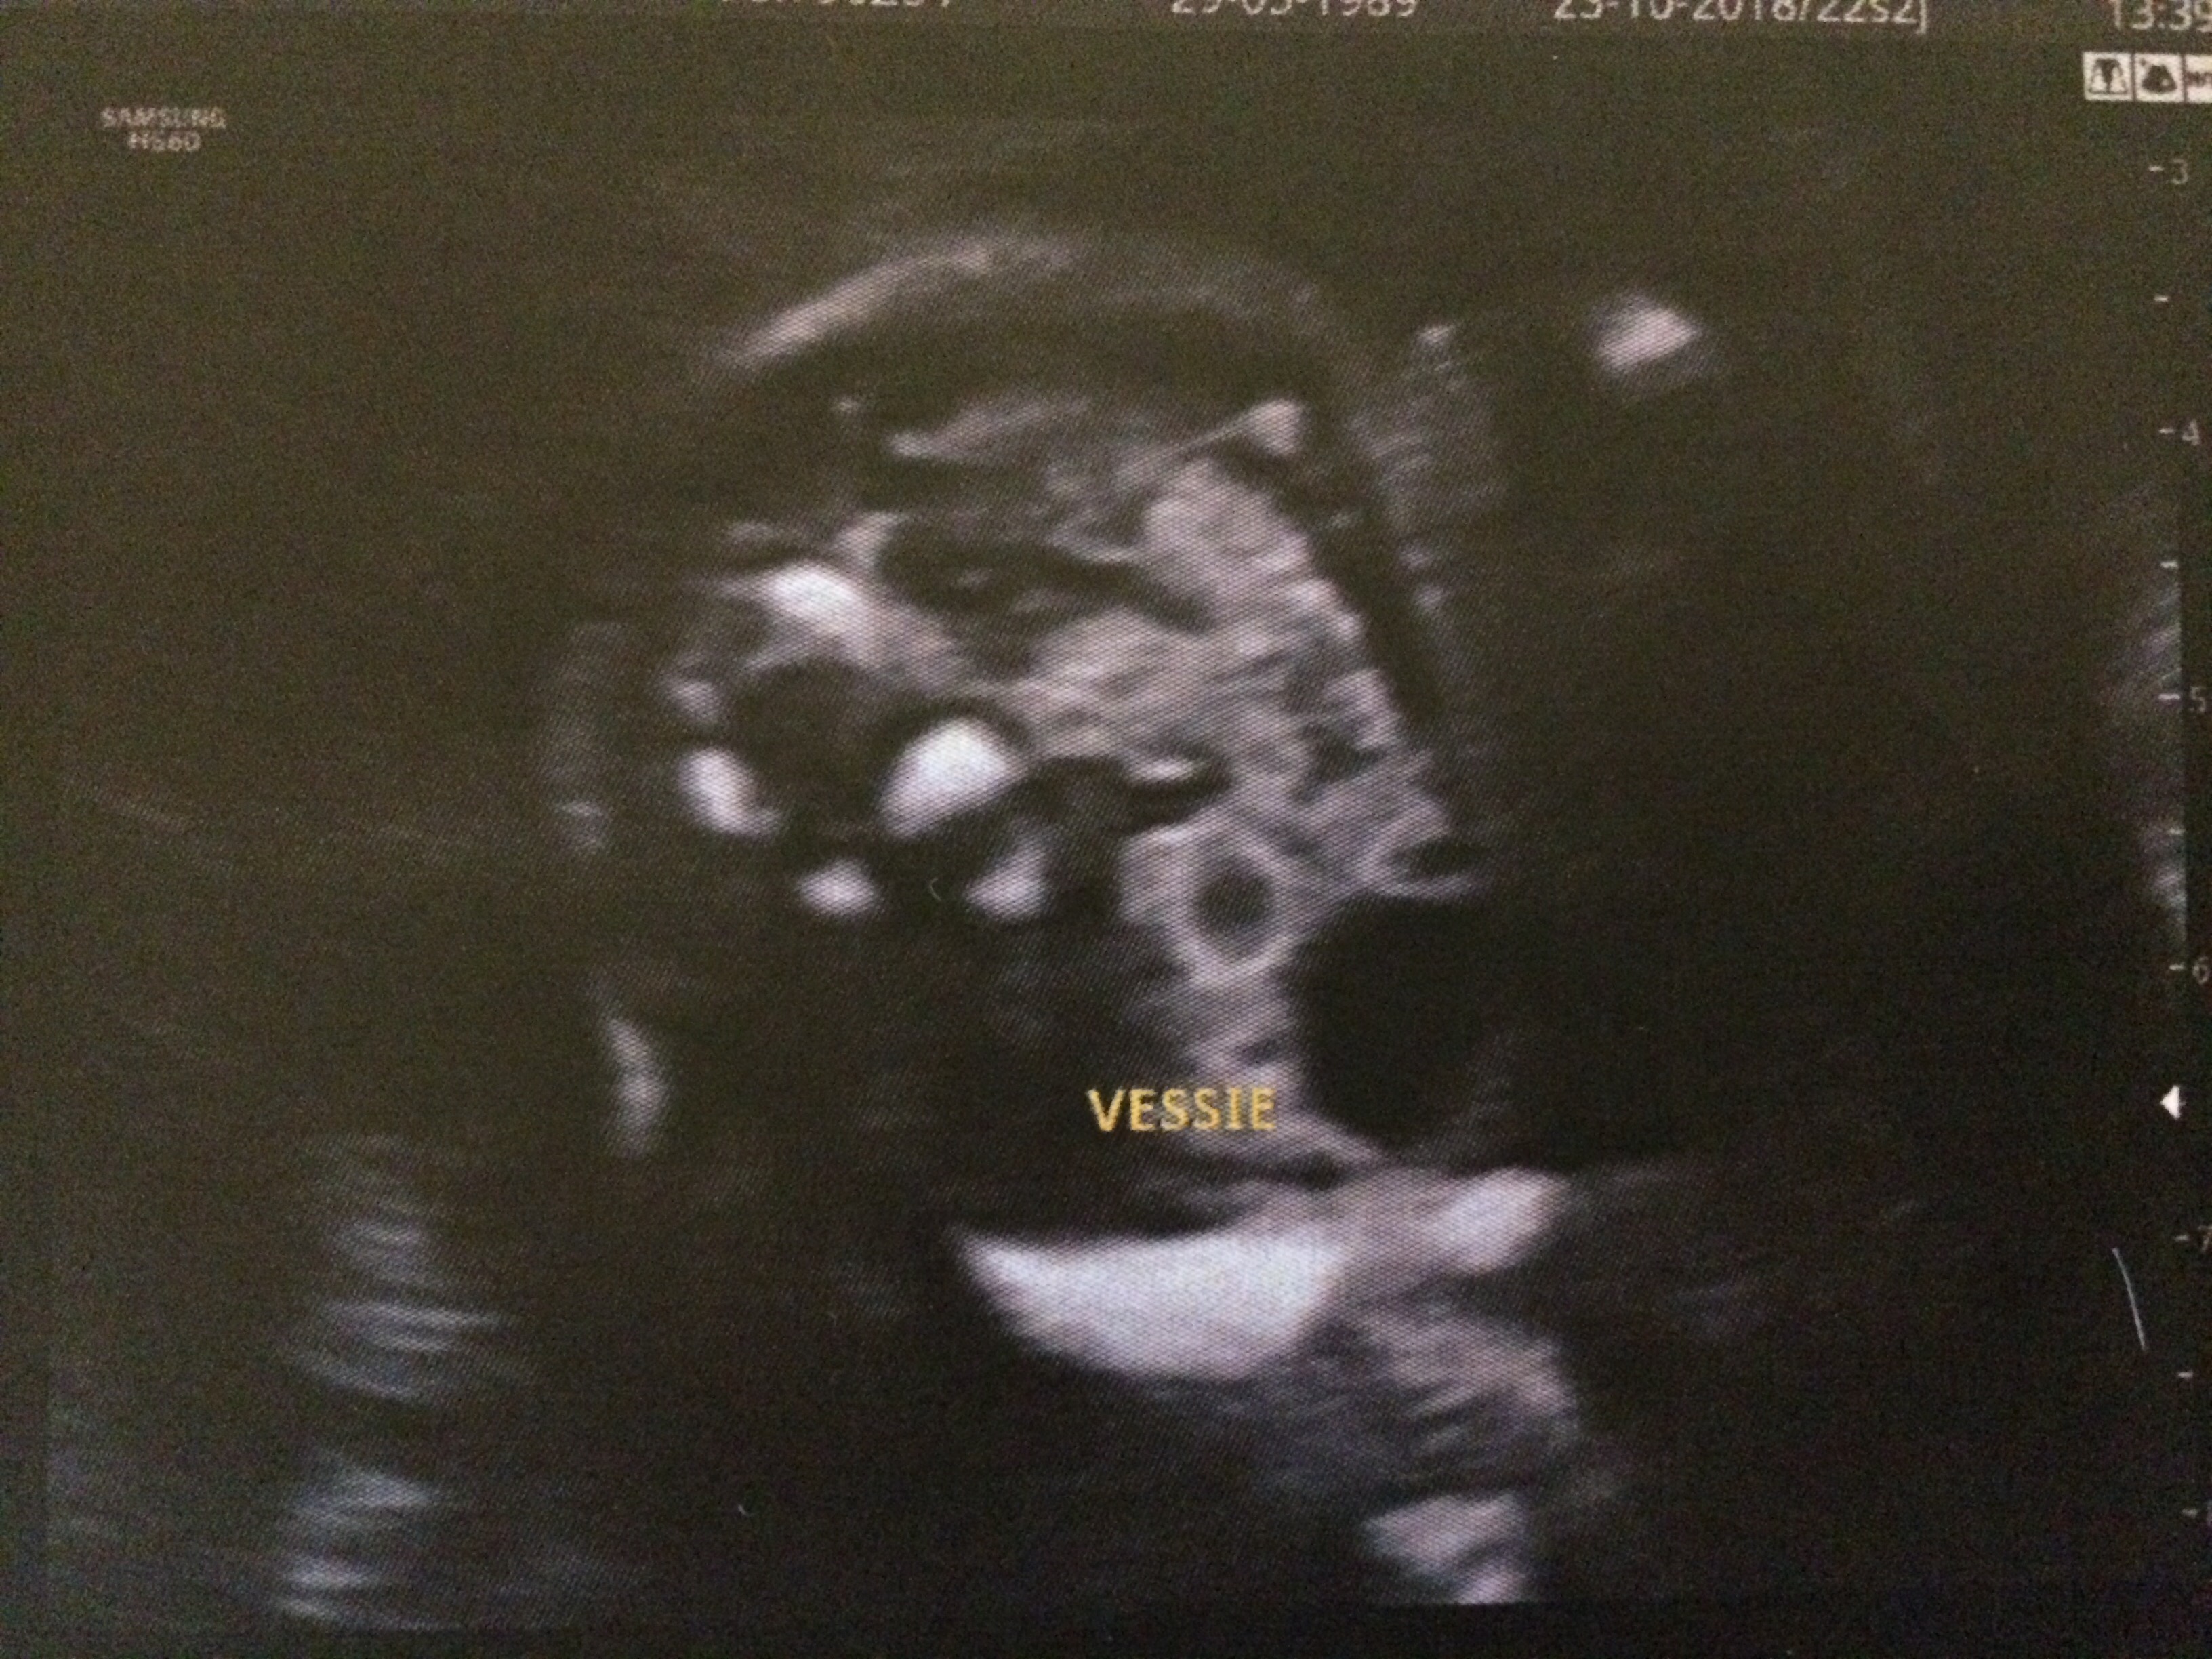

Totally freaking out, told definite girl at 22 weeks but one of the bladder (vessie) shots there looks to be a penis/scrotum imaged. I swayed girl so would be so upset and is getting my very anxious. TBH I don't know exactly where the bladder is imaged or the orientation I just see this huge penis like thing. And the other bladder shot I see nothing. Attachment 41539Attachment 41540